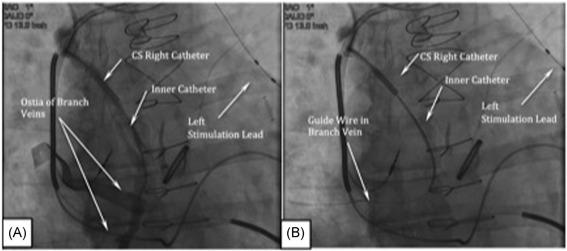

The remedē System is placed in the pectoral region, typically on the right side. A single stimulation lead is placed in either the left pericardiophrenic vein (PPV) or the right brachiocephalic vein (RBC). A sensing lead is placed into the azygous vein to detect respiration.